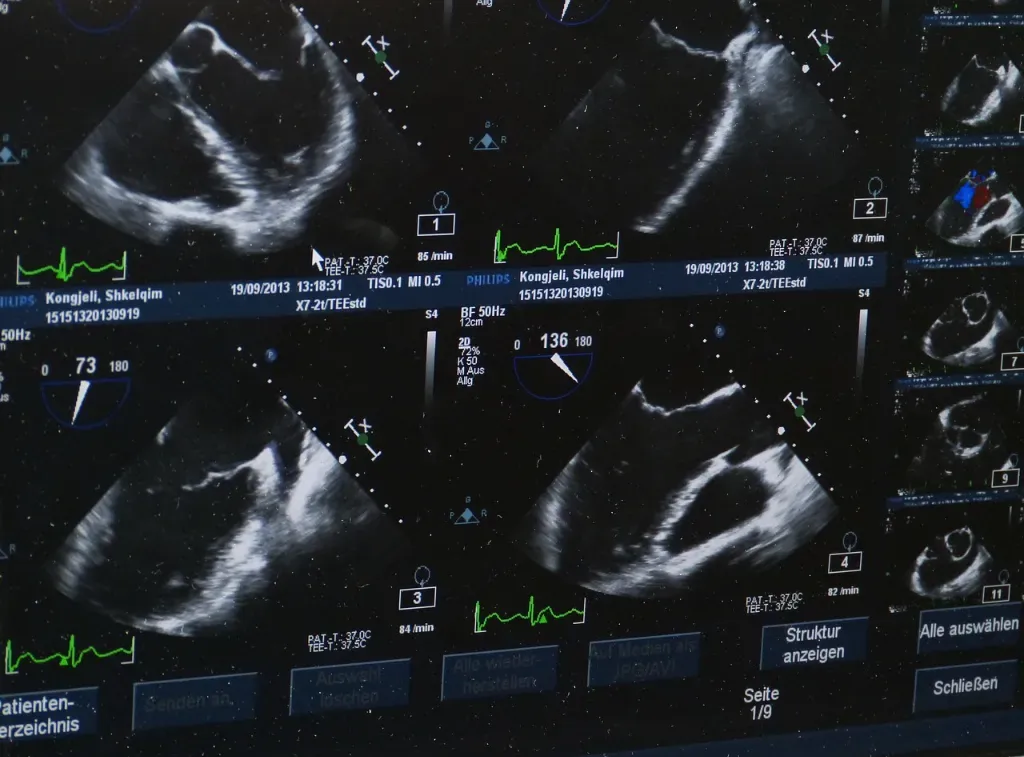

• Głowice sektorowe – często używane w kardiologii, pozwalają na precyzyjne obrazowanie serca.